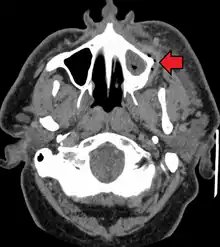

| Destruction of a tooth by dental caries and disease. | |